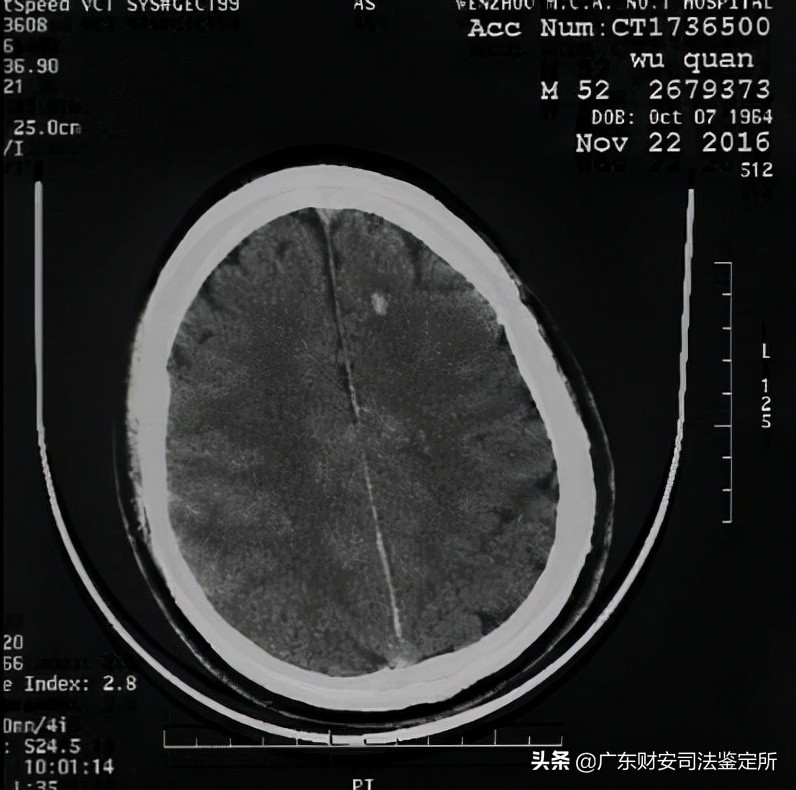

2017 年3月14日 CT片:双侧基底节区及半卵圆中心见多发小片状低密度影,双侧额颞部颅板下见弧形液体信号影,双侧大脑半球脑沟加深、脑回缩小,脑室系统扩大。提示双侧额颞部硬膜下积液,脑萎缩,脑内多发腔梗灶。

(图4,2017年3月14日,双侧额颞部硬膜下积液,脑萎缩,脑内多发腔梗灶)